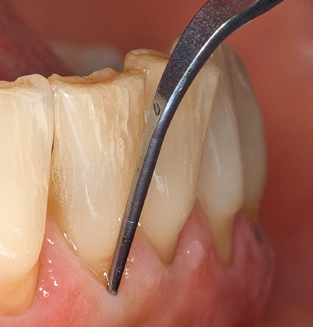

Abb. 4: Für das Sondieren an dentalen Implantaten sind biegsame, millimeterskalierte Sonden empfehlenswert (z.B. Colorvue Kit PCV11KIT6, Hu-Friedy). – Abb. 5a und b: Eine gerade Arbeitsspitze (1P, W&H Dentalwerk Bürmoos GmbH) ist universell für die Instrumentierung natürlicher Zähne geeignet. – Abb. 6: Für die Bearbeitung schwer zugänglicher Bereiche der Zahn- und Wurzeloberflächen (z.B. Furkationen) bieten sich gebogene Arbeitsspitzen (3Pr/3Pl, W&H Dentalwerk Bürmoos GmbH) an. – Abb. 7: Die spitz zulaufende sechseckige Implantatreinigungsspitze (1I, W&H Dentalwerk Bürmoos GmbH) ermöglicht eine atraumatische und effiziente Reinigung der Kronen- und Abutmentoberflächen. – Abb. 8: Für die manuelle Instrumentierung der Implantatoberflächen sind Titan- oder Carbonküretten geeignet.

Nach der maschinellen Reinigung der Zahn­ und Implantatoberflächen erfolgt eine manuelle Instrumentierung der natürlichen Zahnoberflächen mit konventionellen Handinstrumenten. Bei der manuellen Reinigung ist insbesondere auf einen korrekten Anstellwinkel, eine ausreichende Schärfe, eine gute Abstützung und auf eine von apikal nach koronal gerichtete Arbeitsweise der Kürette zu achten. Zur Nachinstrumentierung der Implantatkonstruktionen sollten entweder Titan­ oder Carbonküretten verwendet werden (Abb. 8). Ergänzend zum Einsatz von Ultraschallgeräten können in der Erhaltungstherapie auch Pulverstrahlgeräte genutzt werden. Dabei ist jedoch zu berücksichtigen, dass diese Verfahren nicht zum Entfernen harter Beläge geeignet sind und daher die Verwendung von Hand­ oder Ultraschallinstrumenten nicht komplett ersetzen können. Abschließend erfolgt in jedem Fall eine mechanische Politur der zugänglichen Zahn­ und Implantatoberflächen mit Polierkelchen und Polierpasten (Abb. 9).